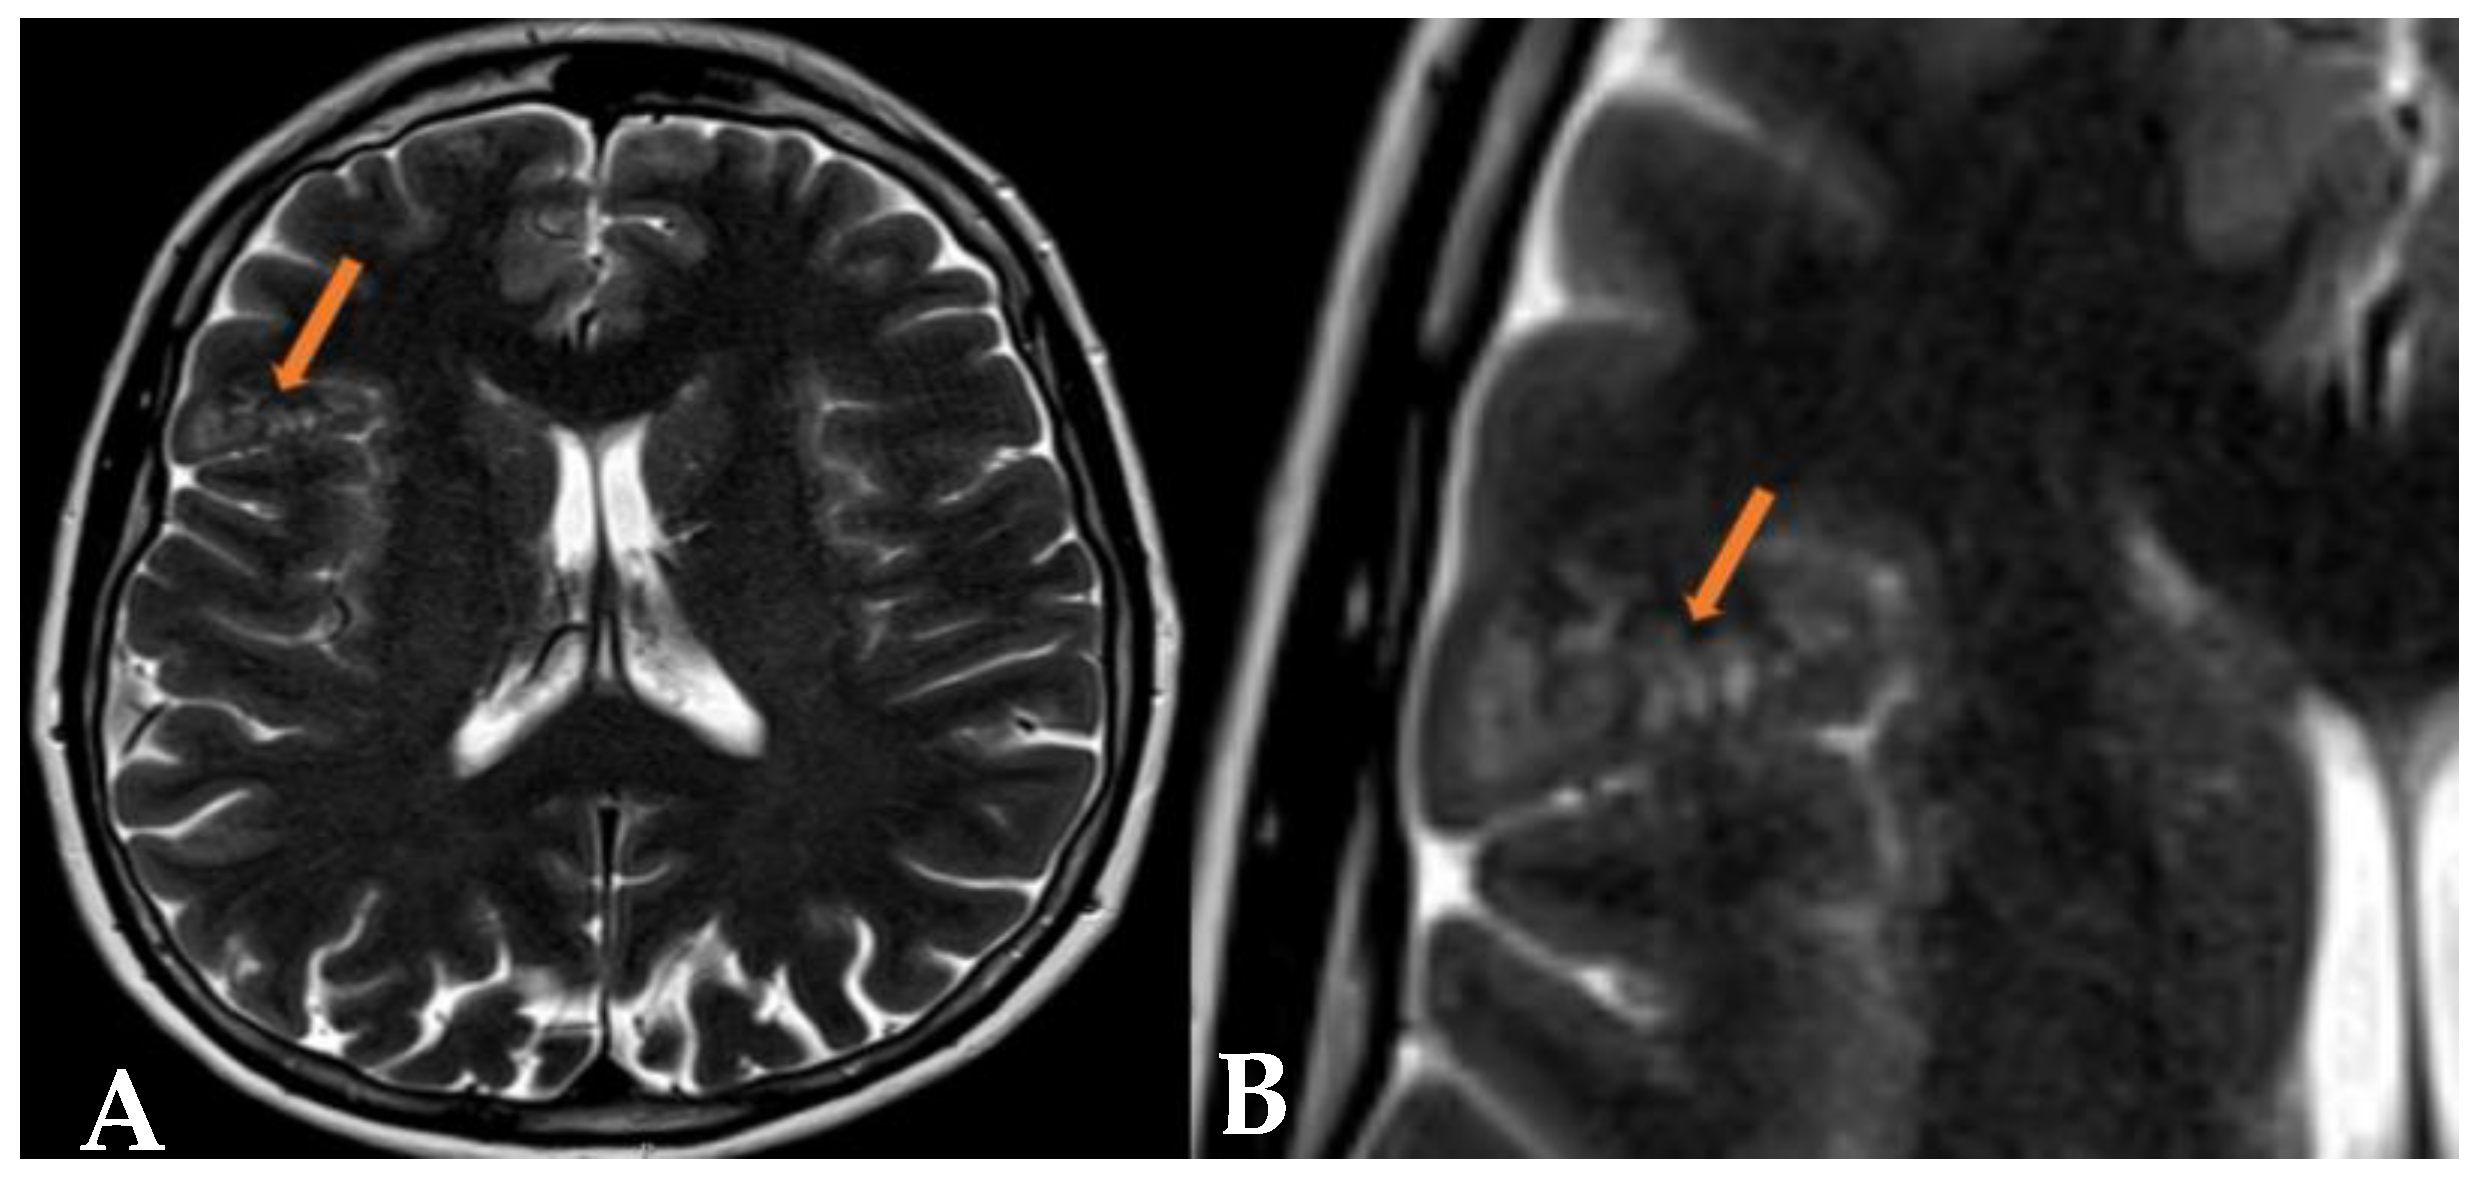

2.1. Case 1

2.2. Case 2